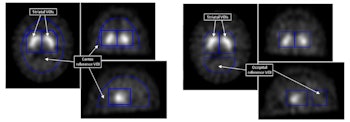

Binding potentials from voxels in striatal VOI were used as features in the support vector machines technique. Cortex and occipital reference VOI were used to calculate them.